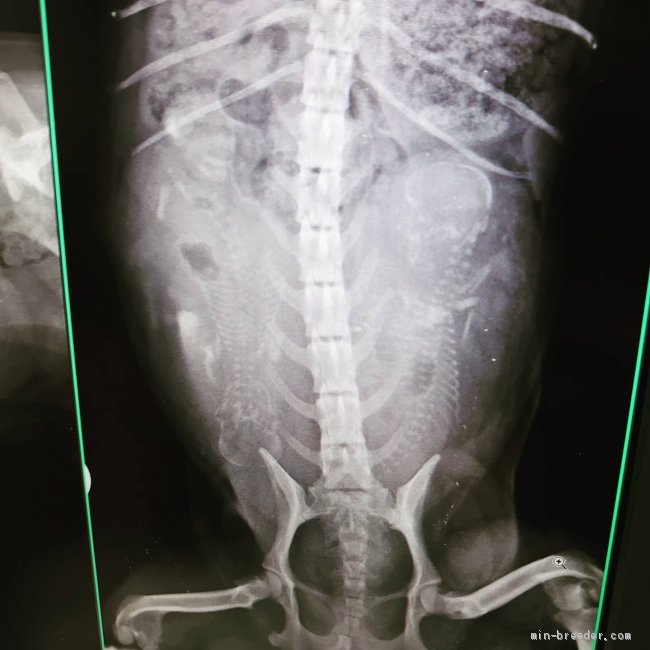

9日にレントゲンに行った結果

2ベビー確認出来ました🤗